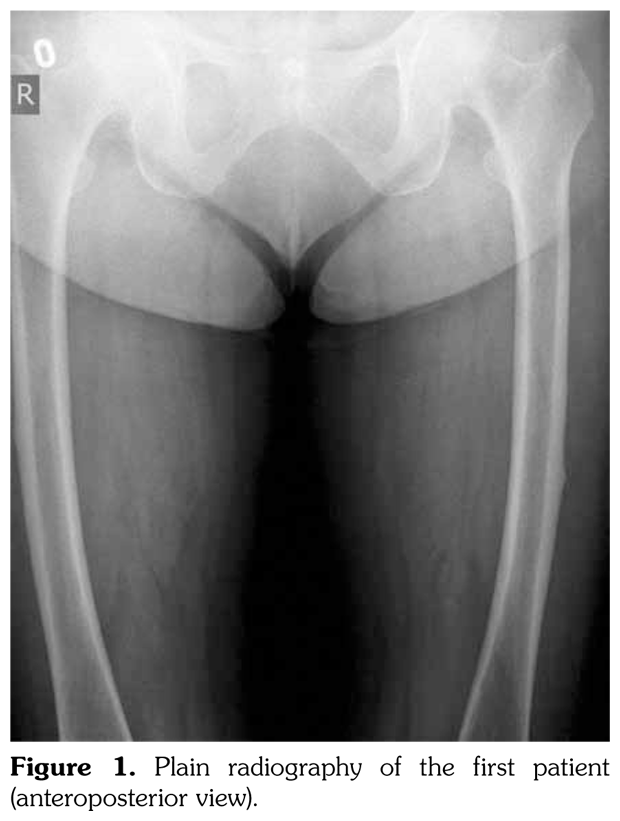

Case 2– A 61-year-old female patient presented with anterior thigh pain and difficulty in walking. Pain severity was 7 over 10 point according to visual analog scale. She had been treated with alendronate 70 mg per week with calcium plus vitamin D for two years. Plain radiographs of femur were taken upon clinical presentation. Cortical stress reaction was detected in both femoral shafts on plain radiographs (Figure 2). Computed tomographic imaging was performed to rule out fracture (Figure 3). Bone scintigraphy showed increased uptake in distal (1)/3 ends of femoral shafts (Figure 4). Serum calcium value was normal and urinary deoxypiridinoline level was mildly increased (46 nM/mMCre).